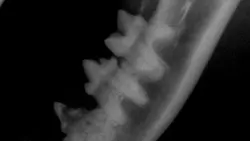

Case 1: Roots of teeth 407 and 409 show evidence of root ankylosis and replacement resorption. A discernable periodontal ligament space is absent. Crowns are affected (Figure 3, left View larger image).